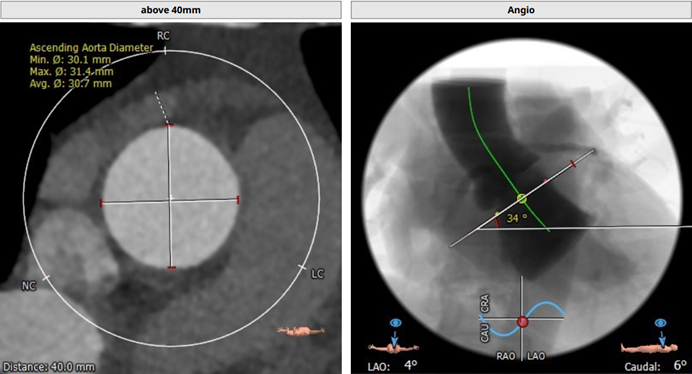

CT评估报告

瓣环平均直径:26.0 mm,左室流出道平均直径:28.1 mm

升主动脉未见明显扩张,心脏角度:34°

左冠开口高度:16.4 mm;右冠开口高度:15.6 mm

钙化积分:606 mm³,重度钙化

左冠瓣叶长度:19.2 mm,右冠瓣叶长度:17.4 mm